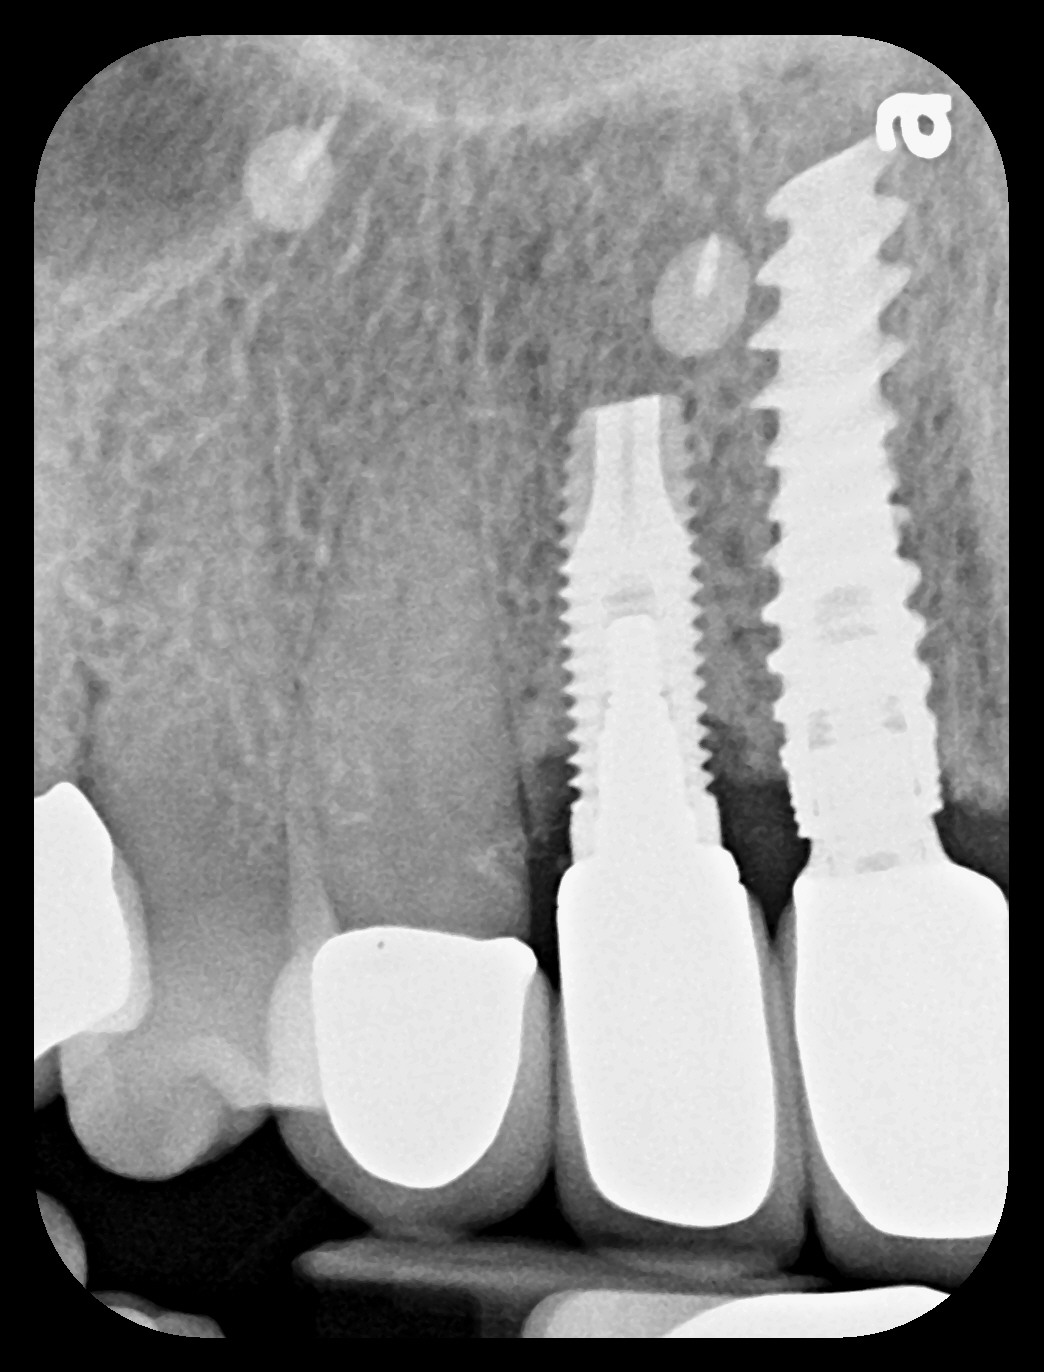

With all of the success seen in the dental community relative to implant placement, dentists are now seeing a more pronounced trend in dental implant care: an increase in the bacteriologic and/or traumatogenic occlusion-mediated loss of tissue integrity, accompanied many times by alveolar bone loss. The most common terminology applied to this condition is peri-implantitis (Figure 1). As replete as the dental literature is with success story after success story, there is virtually no detailed and specific prospective clinical trial data on the diagnosis and management of the peri-implant diseases, which result in soft tissue inflammation and the potential for alveolar bone destruction that may lead to the loss of the implant.

Fig 1. This implant was placed in March 2006. Peri-implantitis was clinically evident in April 2008, with bleeding on probing, suppuration, and increasing probing depth.

Figure 1